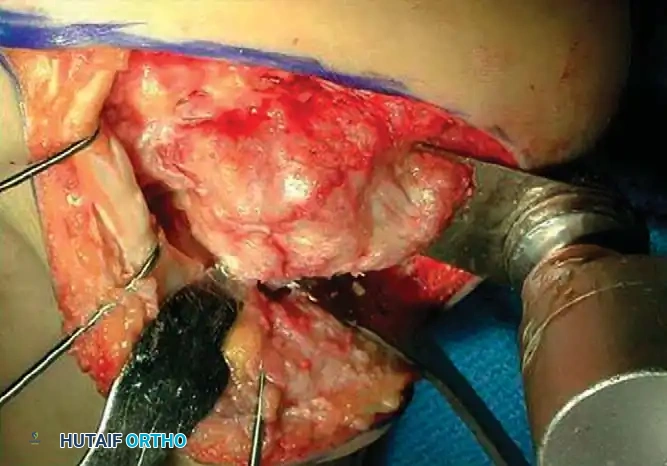

1. Lateral Exostectomy and Decompression

For Type I malunions, the primary issue is lateral impingement.

Intraoperative view demonstrating exposure of the lateral calcaneal wall and preparation for exostectomy.

An extensile lateral approach is utilized to elevate the full-thickness fasciocutaneous flap. The sural nerve and peroneal tendons are identified and protected. The hypertrophic lateral wall of the calcaneus is resected using an osteotome or oscillating saw, thoroughly decompressing the subfibular space.